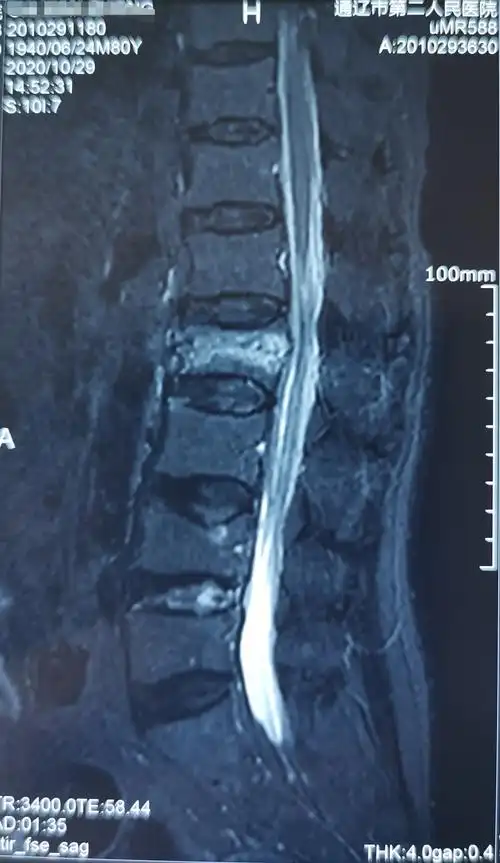

80岁腰椎压缩性骨折患者行椎体成型手术一例